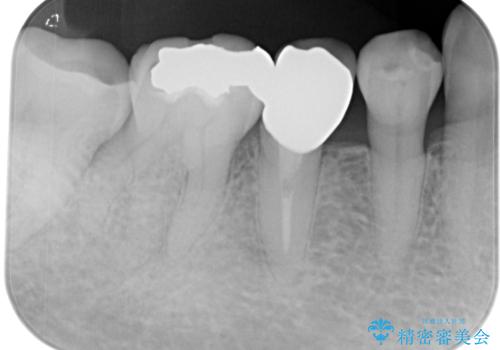

- 食べ物の繊維が引っかかるとのことで来院された患者様です。

ご自身の歯質と金属の詰め物(ゴールドインレー)との間に、わずかに隙間ができていました。

拡大鏡視野下で、ゴールドインレー、虫歯の除去を行い、セラミックインレーに適した形に整えました。